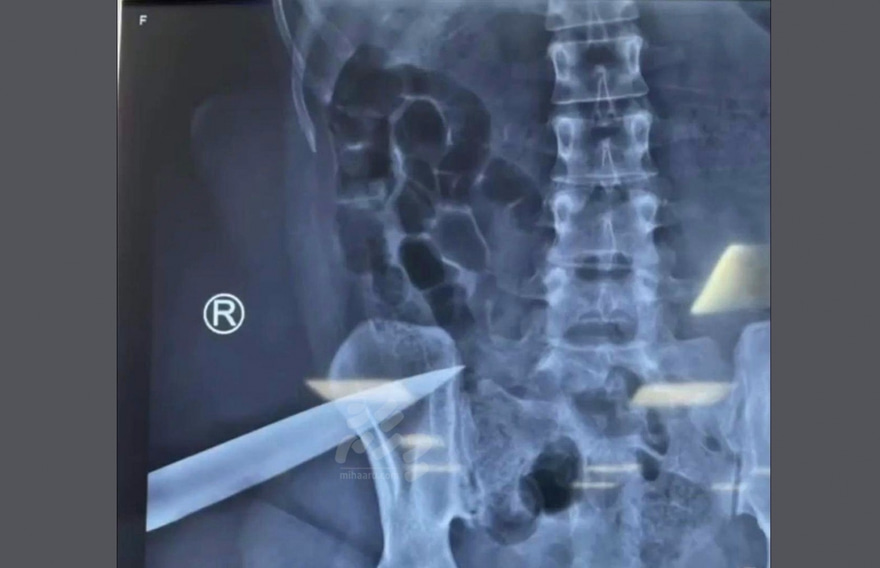

ޒަހަމްވި އަންހެން މީހާގެ އެކްސްރޭ އިން، ފަލަމަސްގަނޑު ތެރޭ އޮތް ވަޅީގެ ތިލަ ފެންނަން

ފުލުހުން ކޯޓުގައި ބުނި ގޮތުގައި އަންހެން މީހާ ހޮސްޕިޓަލަށް ގެންގޮސް ބެލި އިރު ފައިގެ ފަލަމަސްގަނޑުގައި ދެ ޒަހަމެއް ހުއްޓެވެ. އަދި ފަލަމަސްގަނޑު ތެރޭ ވަޅިއެއްގެ ތިލަ އޮތްތަން އެކްސްރޭ އިން ފެނެ އެވެ. ފިރިހެން މީހާ އަމިއްލަ ބަނޑަށް ހެރީ ފުލުހުން ސީނަށް ދިޔައިރު ވެސް ފިރިހެން މިހާ އަތުގައި އޮތް ވަޅިން ކަމަށް ވެސް ފުލުހުން ބުނެފައިވެ އެވެ.